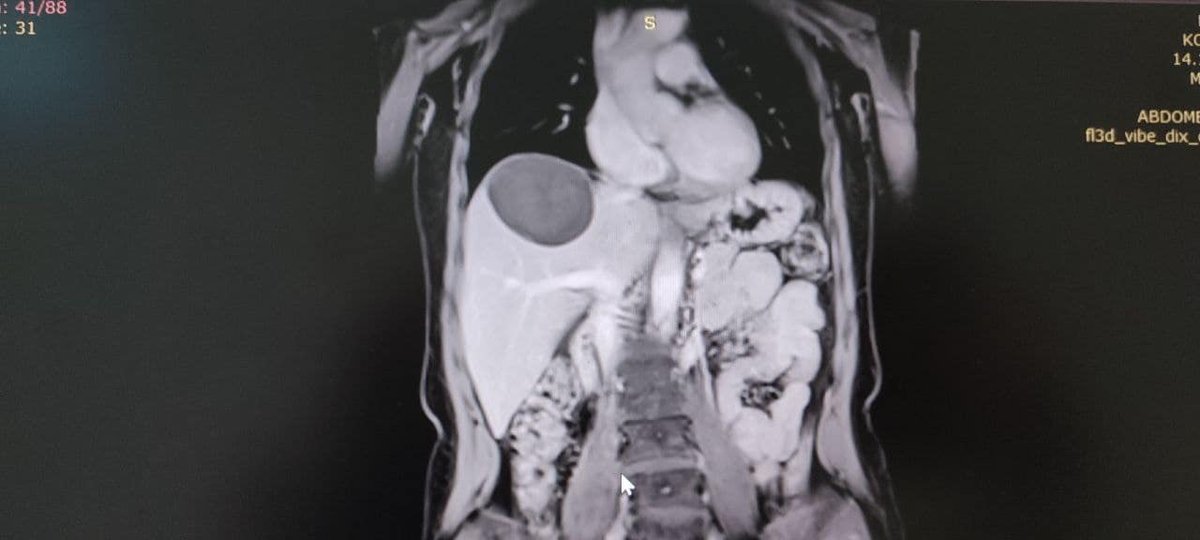

ЩоКіста паразитів у печінці нагадує амніотичний сечовий міхур, в якому дозріває личинки ехінокока. Рак поступово зростає і іноді досягає величезних розмірів (діаметром до 50 см)“, Сказаний У повідомленні. Фахівці Володимир TMO провів операцію та видалив кісту. В даний час у пацієнта все добре.

Прес -служба медичної установи опублікувала фотографію з операційної, але якщо це для вас неприйнятне, не дивіться на вас